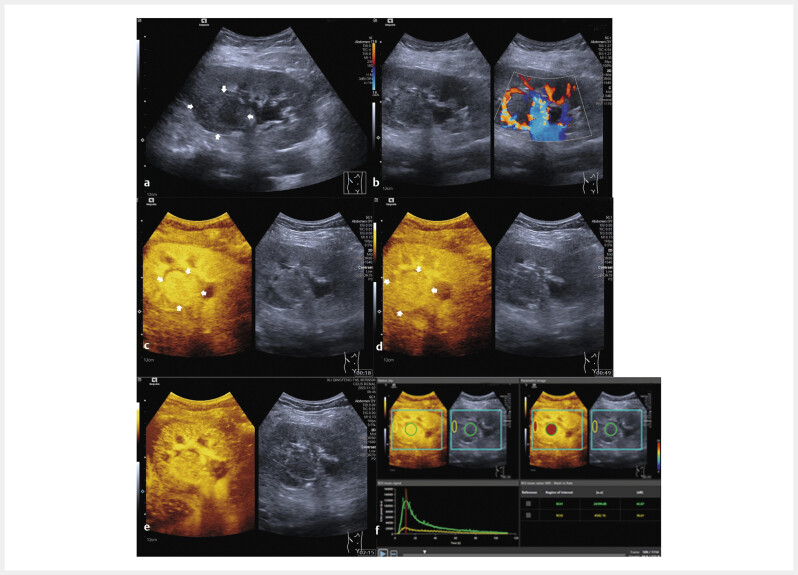

Materials and methods: Patients with surgery resection and histopathologically proven RCC lesions were included. B-mode ultrasound (BMUS) and contrast-enhanced ultrasound (CEUS) were performed one week before surgery. SonoVue was injected as the contrast agent. VueBox (Bracco, Italy) was used for the quantitative analysis. According to the histopathological and immunohistochemical results, patients were classified into two groups: active angiogenesis and inactive angiogenesis. Time intensity curves (TICs) and quantitative parameters were compared between two groups.

Results: From July 2023 to November 2023, a total of 50 patients (13 females and 37 males, mean age 61.1±11.1 years) were included. The mean size of the lesions was 39.4±2.7 mm. Patients were classified into the active angiogenesis group (n=30) and the inactive angiogenesis group (n=20). On BMUS, 68.0% (34/50) of RCCs were visualized as hypoechoic lesions with ill-defined borders and irregular shapes (P>0.05). During cortical phase of CEUS, 72.6% (23/30) of RCCs with active angiogenesis were visualized with hyperenhancement (P=0.027). Only 30.0% (9/30) of RCCs with active angiogenesis showed hypo-enhancement in the parenchymal phase (P>0.05). Compared to the inactive angiogenesis group, TICs of the active angiogenesis group revealed faster and greater enhancement in the cortical phase, slower decline during the parenchymal phase, and an increased area under the curve. Among quantitative parameters, the active angiogenesis group showed the higher ratio of wash-in rate and wash-in perfusion index (P<0.05).

Abstract Image